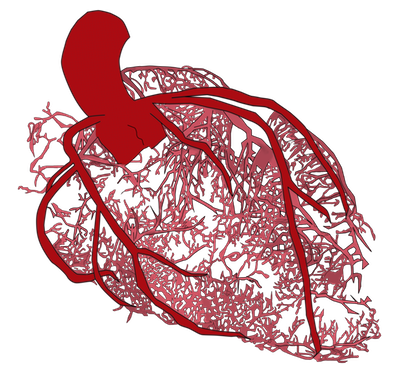

Angina es el nombre que se le da al tipo de dolor en el pecho que la gente siente cuando la mala circulación priva de sangre a su corazón. Al describir las causas de la angina, los médicos a menudo comparan las arterias del corazón con tuberías obstruidas. Podemos pensar en “destapar tuberías” o “liberar una obstrucción” cuando consideramos el procedimiento terapéutico: un stent. Algunas veces las personas tienen angina, pero sus arterias coronarias no están obstruidas. La analogía de un tubo obstruido entonces deja de tener sentido. Esto no es sorprendente, porque la circulación del corazón es mucho más complicada que la de los tubos rígidos de metal. El problema ahora está en otra parte: en los pequeños capilares que penetran en el músculo cardíaco para nutrirlo de sangre.

Para entender cómo ocurre el síndrome cardiaco X, necesitamos hacer un breve recorrido por el interior del músculo cardíaco y ver cómo funciona su circulación en términos generales. Las arterias que alimentan el corazón con sangre son mucho más que tubos metálicos rígidos. Las arterias funcionan de forma muy parecida a los grandes órganos del cuerpo: reaccionan al entorno y modifican su función según sea necesario. Cuando hacemos ejercicio, la demanda de energía y oxígeno del cuerpo aumenta, por lo que el corazón comienza a bombear más rápido y más fuerte. Cuando la sangre comienza a fluir a través de las arterias que alimentan el corazón, las paredes de estas arterias se estiran. Este estiramiento provoca la liberación de sustancias que viajan por la corriente, dirigiendo los pequeños capilares que penetran el músculo para que se rellenen y reciban y entreguen más sangre. La mayor cantidad de sangre que se inyecta en el músculo cardíaco le permite contraerse más fuerte y más rápido. La disfunción microvascular es un problema causado por la interrupción de este proceso. Cuando una persona que sufre de síndrome cardiaco X hace ejercicio, los capilares que alimentan de sangre al músculo no funcionan como se supone que deberían. No se rellenan para entregar más sangre, por lo que el músculo cardíaco debe luchar sin el suministro de sangre que necesita. Esto causa angina y dificultad para respirar. Los mecanismos que hacen que los diminutos vasos sanguíneos del corazón se engrosen cuando es necesario son complejos y se comprenden de manera incompleta. Sin embargo, se sabe que hay varios aspectos diferentes relacionados con el problema: